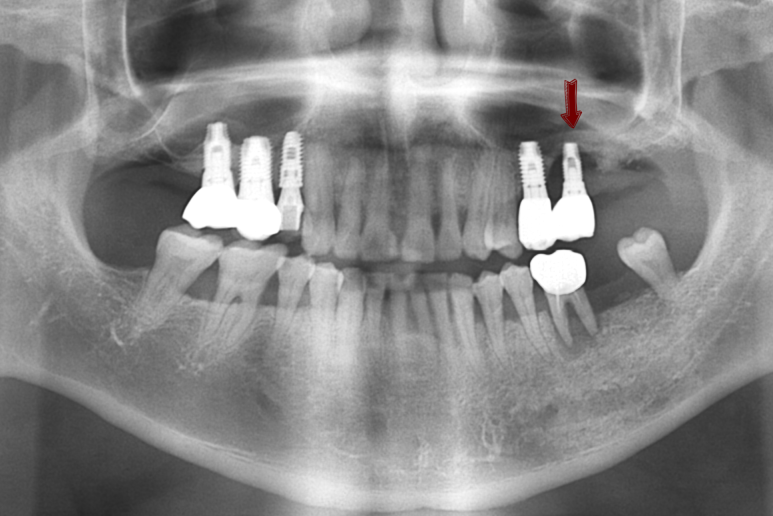

원장님 아버지 케이스입니다[!]

원장님이 해외에서 공부중일 때 다른 치과에서 임플란트를 여러개 하셨는데요

빨간색 화살표로 표시한 부분의 인플란트 주변 뼈가 녹아서 임플란트가 흔들리는 상태였습니다.

화살표 부위 치아 외에 뒤에 치아가 원래 하나더 있어야 개수가 맞기 때문에

임플란트 2개를 더 있어야하는데

아마 고난도의 상악동 거상술이 필요해서 다른 치과에서 임플란트를 뼈가 그나마 있는 화살표 부분에만 심었던 것 같습니다.